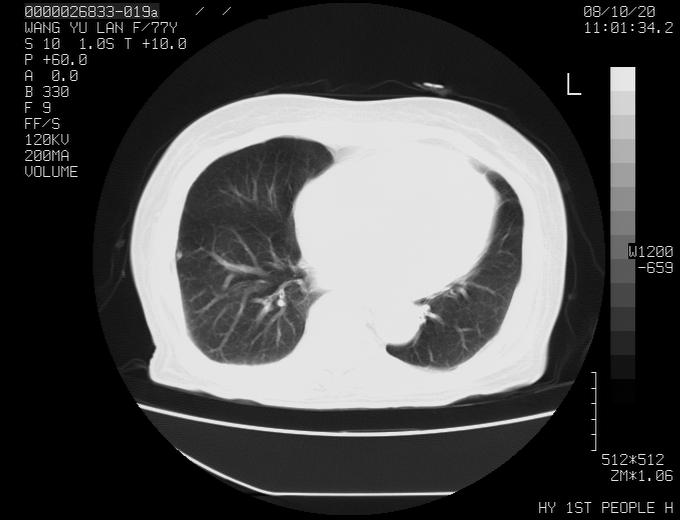

女性,77岁,胸部疼痛半月。左上肺团块影,本人考虑血管畸形,请分析

非常典型的avm(谢谢楼主,收藏了)

左上叶前段多发结节肿块并前段支气管息肉样结节、上叶腋亚段阻塞性肺炎,以结核可能性大。

纵隔有多个淋巴结肿大,提示周围型肺癌并转移可能性大。

动脉期未见大血管同步强化,首先考虑周围型肺癌

动脉期病灶近中线侧可见星芒状与大血管同等强化密度,支持考虑血管畸形伴血栓形成,动脉期不曲型,不除外周围型肺癌

1、考虑avm可能性大。2、纵隔有肿大淋巴结,左肺上叶有炎性病变,不排除肺癌并转移可能。